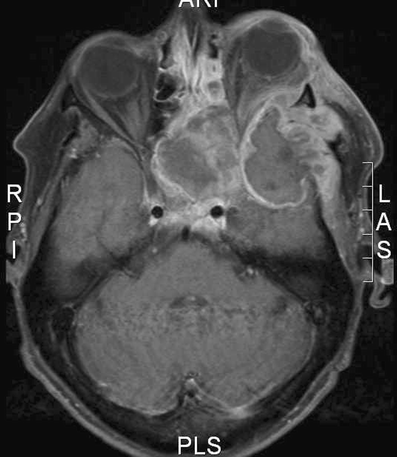

Histopathological investigation revealed a plasmablastic lymphoma. Because this disease is AIDS-related, an HIV test was conducted, which proved to be positive. Postoperatively, magnetic resonance imaging (MRI) was made to exclude cavernous sinus thrombosis and to better assess the extension of the diagnosed pathology. Multiple masses were seen (Fig. 4). There was encroachment upon the cavernous sinus and infiltration into the orbit, but no signs of cavernous sinus thrombosis.

Fig. 4

figure 4

Axial magnetic resonance image showing huge plasmablastic lymphoma infiltrating the left orbit